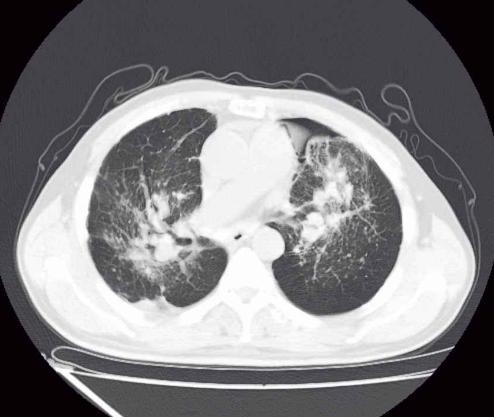

- 胸部影像学检查显示与活动性肺结核相符的病变。

- 胸部影像学显示与活动性肺结核相符的病变,患者有咳嗽、咳痰、咯血等肺结核的可疑症状。

- 胸部影像学检查显示与活动性肺结核相符的病变,PPT试验强阳性或γ-干扰素释放试验(又叫T-SPOT)阳性。

- 胸部影像学检查显示与活动性肺结核相符的病变,经过诊断性抗菌治疗两周无效,或随访检查可以排除其他原因导致的肺部疾病者。